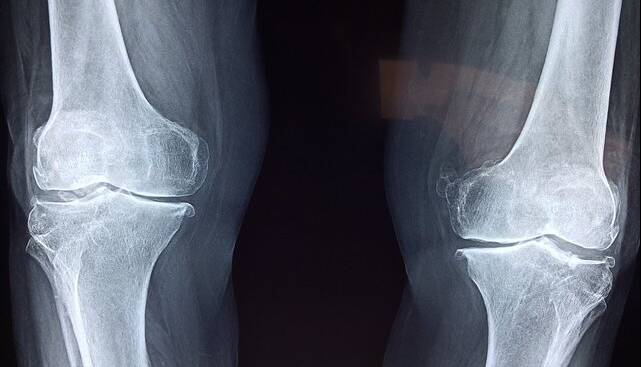

آذربانی در خصوص روشهای تشخیص بیماری توضیح داد: تشخیص پوکی استخوان با انجام سنجش تراکم استخوان (BMD) یا دگزا (DEXA) انجام میشود. این تست ساده و بدون درد، میزان تراکم مواد معدنی در استخوان را میسنجد و با کمترین میزان اشعه انجام میشود. حتی در زنان باردار نیز در شرایط خاص قابل انجام است. همه خانمهای بالای ۶۵ سال و آقایان بالای ۷۰ سال باید بدون هیچ پیششرطی این تست را انجام دهند.